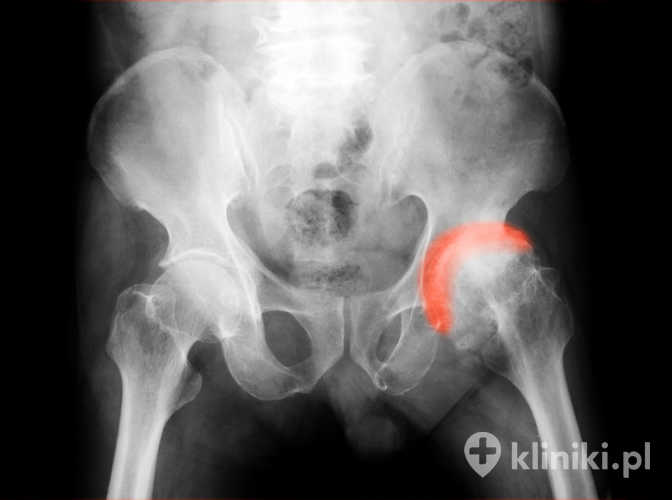

Do zwyrodnienia stawów dochodzi w przypadku zaniku chrząstki stawowej i odsłonięcia części kostnych. Jak w każdym rodzaju choroby zwyrodnieniowej stawów, również w przypadku choroby zwyrodnieniowej stawu biodrowego, określanej też jako koksartroza, można wskazać czynniki etiologiczne odpowiedzialne za jej rozwój - mówimy wówczas o koksartrozie wtórnej.

Zwyrodnienie stawu biodrowego od dłuższego czasu można skutecznie leczyć za pomocą alloplastyki. Zabieg polega na wymianie niesprawnych elementów stawu biodrowego na sztuczne, które z czasem zrastają się z kośćmi pacjenta. Alloplastyka przywraca ruchomość stawu, pozwala na powrót do normalnego funkcjonowania oraz niweluje ból.

Odsłonięte powierzchnie stawowe kości są narażone na tarcie, co powoduje rozwój zmian, w tym sklerotyzacji podchrzęstnej oraz rozwoju torbieli podchrzęstnych. Z czasem dochodzi do powstania wyrośli kostnych, do wtórnej reakcji zapalnej w błonie maziowej, zmian elastyczności torebki stawowej oraz wiązadeł.

Warto pamiętać: Zwyrodnienie stawów charakteryzuje się zanikiem chrząstki stawowej i podchrzęstnej warstwy kości, rozwojem torbieli podchrzęstnych oraz wyrośli kostnych. Ból i trudności z chodzeniem wynikają głównie z przeciążenia uszkodzonych struktur, a u części pacjentów mogą pojawiać się także wtórne, miejscowe reakcje zapalne błony maziowej, które nasilają dolegliwości.